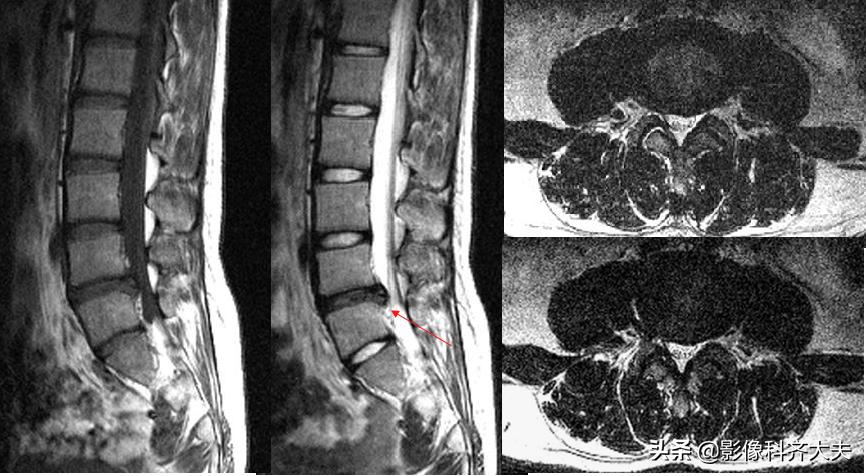

MRI:腰4、5间盘变性、突出,硬膜囊受压

MRI:腰椎间盘突出

MRI:腰 5-骶1间盘脱出

MRI:腰椎间盘脱出

MRI:髓核游离